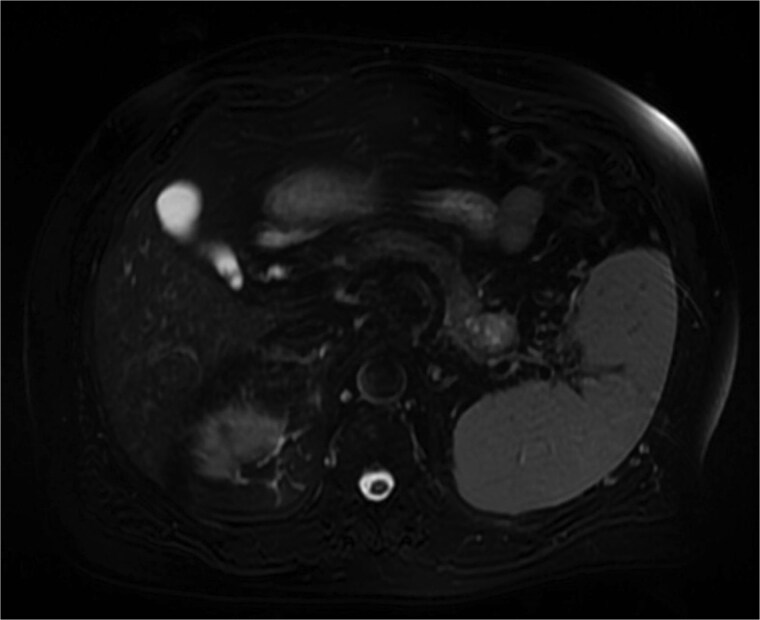

摘要胰腺是肾细胞癌发生远端转移的罕见部位。我们报告一名68岁男性,因肾细胞癌而行左侧根治性肾切除术,术后4年的常规随访影像中发现胰腺尾部有孤立的胰腺转移。患者最初接受帕唑帕尼治疗,但由于胰腺病变进行性生长,无其他转移部位,因此给予立体定向消融体放疗(SABR),在SABR后12个月完全缓解。

The pancreas is a rare site of distant metastasis from renal cell carcinoma. We present the case of a 68-year-old man with a prior history of left radical nephrectomy for renal cell carcinoma, who was found to have an isolated pancreatic metastasis in the pancreatic tail during routine follow-up imaging 4 years postsurgery. The patient was initially managed with pazopanib, but due to progressive growth of the pancreatic lesion without other metastatic sites, stereotactic ablative body radiotherapy (SABR) was given, with complete response at 12 months after SABR.